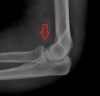

X-ray : 구상돌기 골절(Coronoid process fracture)